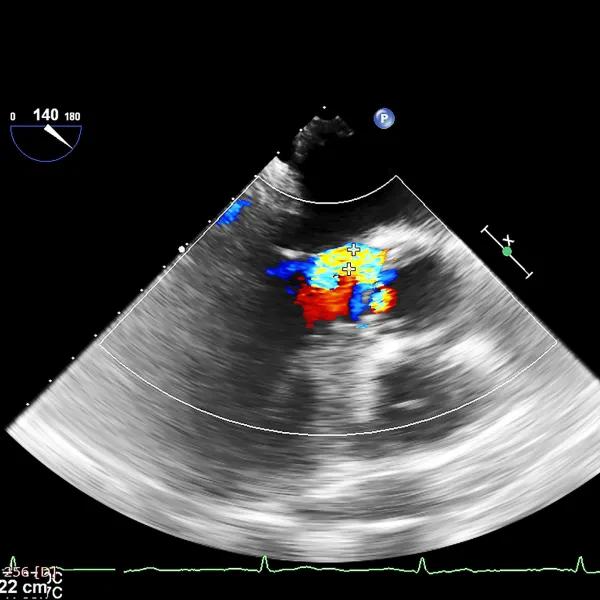

Third, long-term high blood pressure damage to the heart. It is the enlargement of the left ventricle hypertrophy, which eventually leads to a decrease in systolic and diastolic function, and aortic regurgitation insufficiency. Cardiac color ultrasound examination can objectively reflect the changes in the structure and function of the heart, and can be used as a routine physical examination item every year.